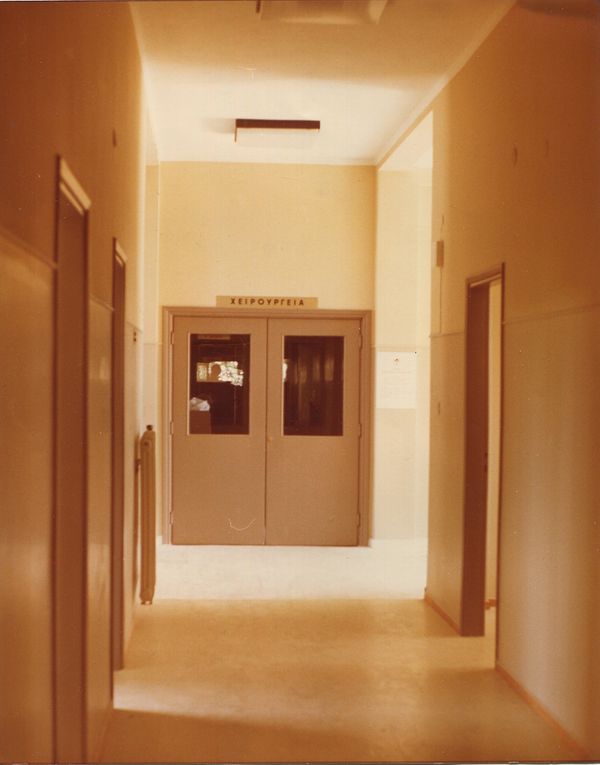

In this way, the concept of the laboratory space was introduced into my research. These spaces function as places of memory but also as scenes where the people who shaped my family environment appear.

My grandfather, through the practice of orthopedics, develops a relationship that is linked to the observation and analysis of forms. And my grandmother, who through sculpture, transforms thoughts into three-dimensional form.

The laboratory is not only a physical place, but an interpretive framework within which memory takes shape and can be read as “frames” in the sense attributed by Hirsch, that is, frames that organize the narration of family history and determine what is preserved and what is silenced.